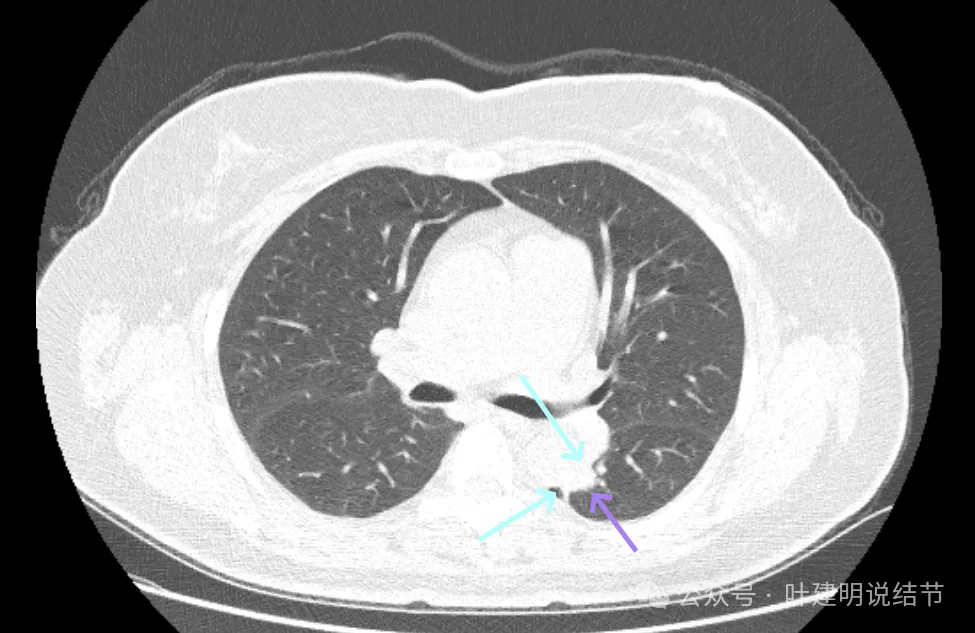

先看2019年时的影像:

病灶出现,密度不纯,有点状高密度成分,表面不光滑不平整。

实性成分为主,但边缘缺乏膨胀性,长刺较细长,感觉更像慢性炎。

此层不是很像炎症,有一定膨胀性。黄色箭头处示有细支气管被病灶截断似的;紫色箭头示略有小的毛刺征;但绿色箭头所指的胸膜有增厚的表现,而且蓝色箭头指的条状不锐利,这又与炎性病变并影响邻近胸膜是符合的。

上图密度较高,大部分实性,灶内略杂乱,与主动脉壁之间稍有缝隙,对应胸膜略有增厚,整体轮廓较清。

这样的病灶首次发现,虽不能完全除外恶性,但慢性炎的解释相对更符合些,肯定是要先随访观察或消炎后复查再对比。